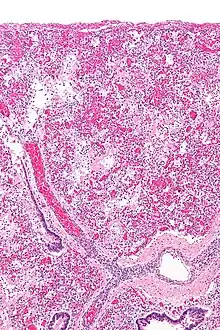

Micrograph of diffuse alveolar damage, the histologic correlate of ARDS. H&E stain.

ARDS is a form of fluid accumulation in the lungs not explained by heart failure (noncardiogenic pulmonary edema). It is typically provoked by an acute injury to the lungs that results in flooding of the lungs' microscopic air sacs responsible for the exchange of gases such as oxygen and carbon dioxide with capillaries in the lungs.[13] Additional common findings in ARDS include partial collapse of the alveoli(atelectasis) and low levels of oxygen in the blood (hypoxemia). The clinical syndrome is associated with pathological findings including pneumonia, eosinophilic pneumonia, cryptogenic organizing pneumonia, acute fibrinous organizing pneumonia, and diffuse alveolar damage (DAD). Of these, the pathology most commonly associated with ARDS is DAD, which is characterized by a diffuse inflammation of lung tissue. The triggering insult to the tissue usually results in an initial release of chemical signals and other inflammatory mediators secreted by local epithelial and endothelial cells.

Neutrophils and some T-lymphocytes quickly migrate into the inflamed lung tissue and contribute in the amplification of the phenomenon. The typical histological presentation involves diffuse alveolar damage and hyaline membrane formation in alveolar walls. Although the triggering mechanisms are not completely understood, recent research has examined the role of inflammation and mechanical stress.